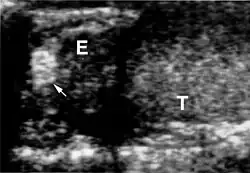

Die Diagnose VHL-Syndrom wird beim Vorhandensein von kapillären Hämangioblastomen (gefäßreichen Tumoren) im ZNS oder der Netzhaut des Auges gestellt. Weitere zum VHL-Komplex gehörende Tumoren (Phäochromozytom, Nierenzellkarzinom) oder eine entsprechende Familienanamnese treten hinzu. In der Kernspintomografie stellen sich die Hämangioblastome als kontrastmittelaufnehmende Knötchen dar.

Das klinische Spektrum der Erkrankung umfasst neben den Affektionen von Augen und Kleinhirn das Auftreten von Hämangioblastomen im Bereich des Hirnstamms und des Rückenmarkes. Sodann werden Nierenzellkarzinome (Erkrankungsrisiko liegt bei 25 – 45 %, meist ab dem 50. Lebensjahr), Pankreaszysten, Phäochromozytome, Nebenhodenzysten und eine Polyzythämie beobachtet.

Die Hämangioblastome des ZNS präsentieren sich in ca. 60 % der Fälle im Kleinhirn, in 13 % der Fälle im Rückenmark und in 4 % der Fälle im Hirnstamm sowie selten < 1 % im Großhirn. Die Läsionen im Kleinhirn werden im Schnitt bei Patienten im Alter von 29 Jahren klinisch auffällig und im Fall von Rückenmarksläsionen im Alter von 34 Jahren.